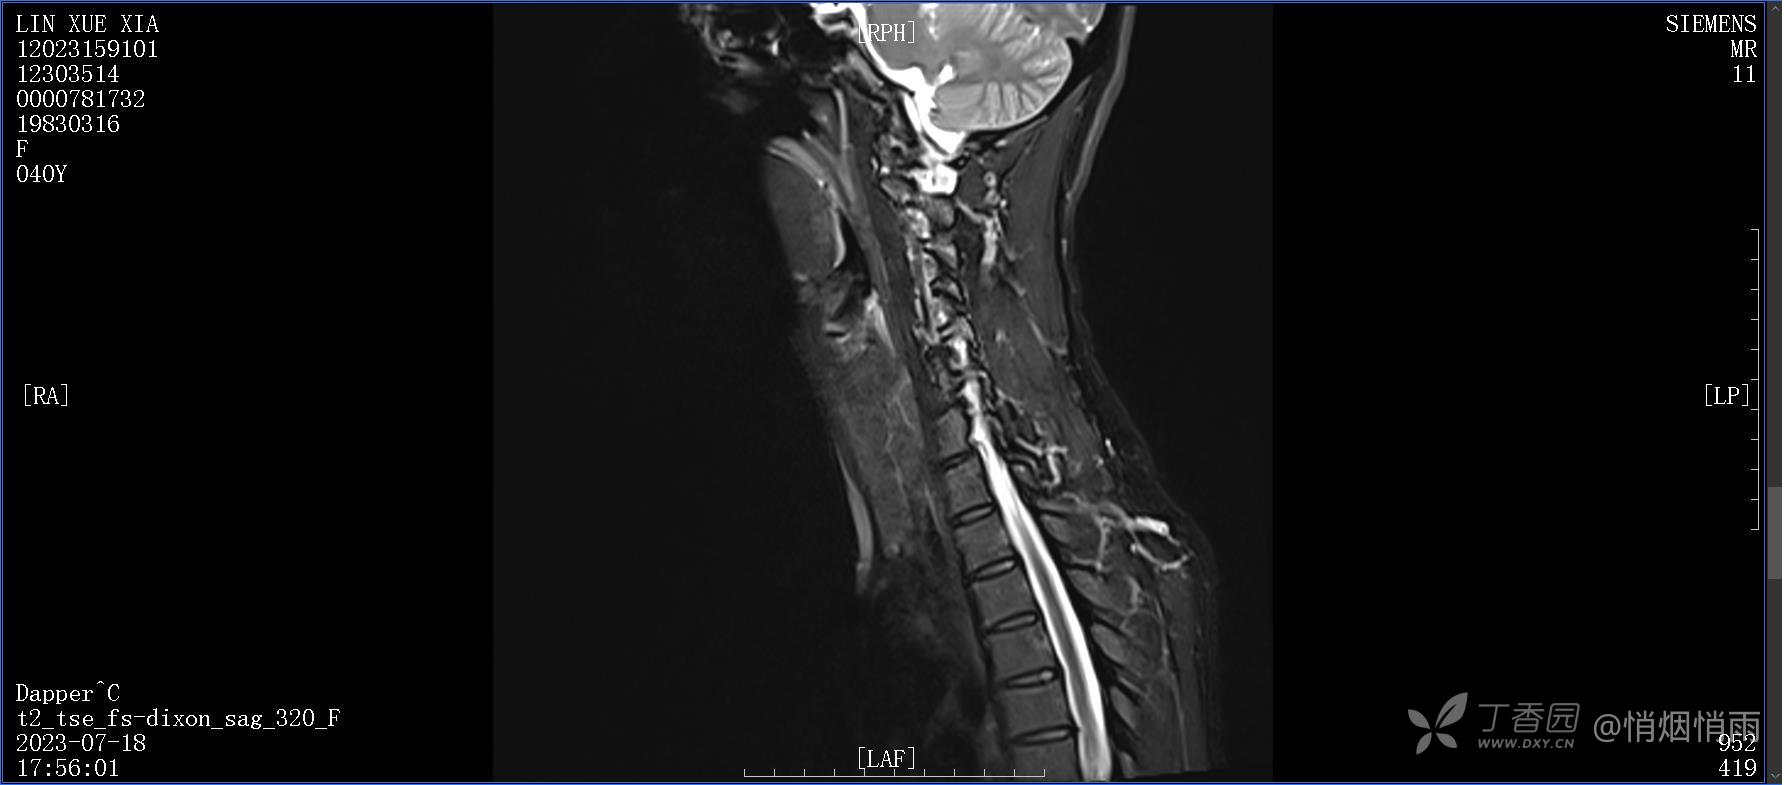

不明原因的右肩背部疼痛

NeurothinkerZ 推荐患者女性,40岁,因右肩背部疼痛班活动受限4日余入院(2023-07-17)。

病史:入院前4天无明显诱因突然感右肩背疼痛伴随活动受限,自行口服依托考昔、艾瑞昔布等药物治疗,院外应用肩关节局部手法按摩等,均无明显改善。外院门诊诊为颈椎病。自诉既往多次“胸椎小关节紊乱”于当地诊所行手法按摩,治疗后好转,否认慢性疾病病史、外伤史、手术史,诉青霉素过敏,无其他药物食物过敏史,否认吸烟史、饮酒史,月经正常,经量正常。

目前的诊断,暂时依据辅助检查诊为肩袖损伤,但是患者疼痛的性质和特点,却不是单纯的肩袖损伤所致。考虑过胸廓出口综合征,但是该疾病会出现肩胛区的疼痛吗?(由于考虑到费用的问题,没再进行下一步的检查)带状疱疹会有如此的症状吗?